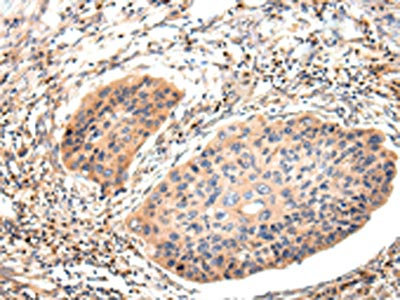

The image on the left is immunohistochemistry of paraffin-embedded Human esophagus cancer tissue using CSB-PA278626(Lambda Light chain Antibody) at dilution 1/20, on the right is treated with synthetic peptide. (Original magnification: ×200)

The image on the left is immunohistochemistry of paraffin-embedded Human thyroid cancer tissue using CSB-PA278626(Lambda Light chain Antibody) at dilution 1/20, on the right is treated with synthetic peptide. (Original magnification: ×200)